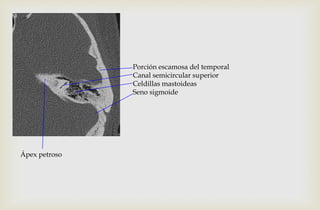

Porción escamosa del temporal

Canal semicircular superior

Celdillas mastoideas

Seno sigmoide

Ápex petroso